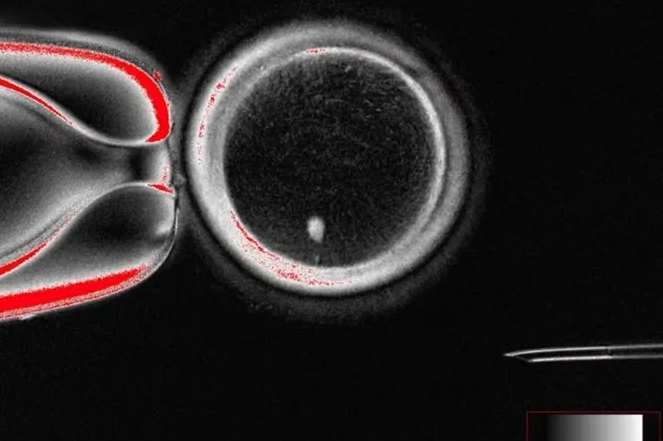

Яйцеклетка с ядром клетки кожи человека до оплодотворения. Mitalipov Laboratory

Ученые извлекали ядро из обычной клетки кожи и пересадили его в донорскую яйцеклетку, лишенную собственного ядра. Главной задачей было добиться правильного числа хромосом — половые клетки должны содержать 23 хромосомы, а не 46, как обычные клетки тела. Команда разработала метод «митомейоза», имитирующий естественное деление клетки так, чтобы один набор из 23 хромосом отбрасывался. В результате удалось создать 82 функциональные ооциты (клетки, из которых развиваются зрелые яйцеклетки).